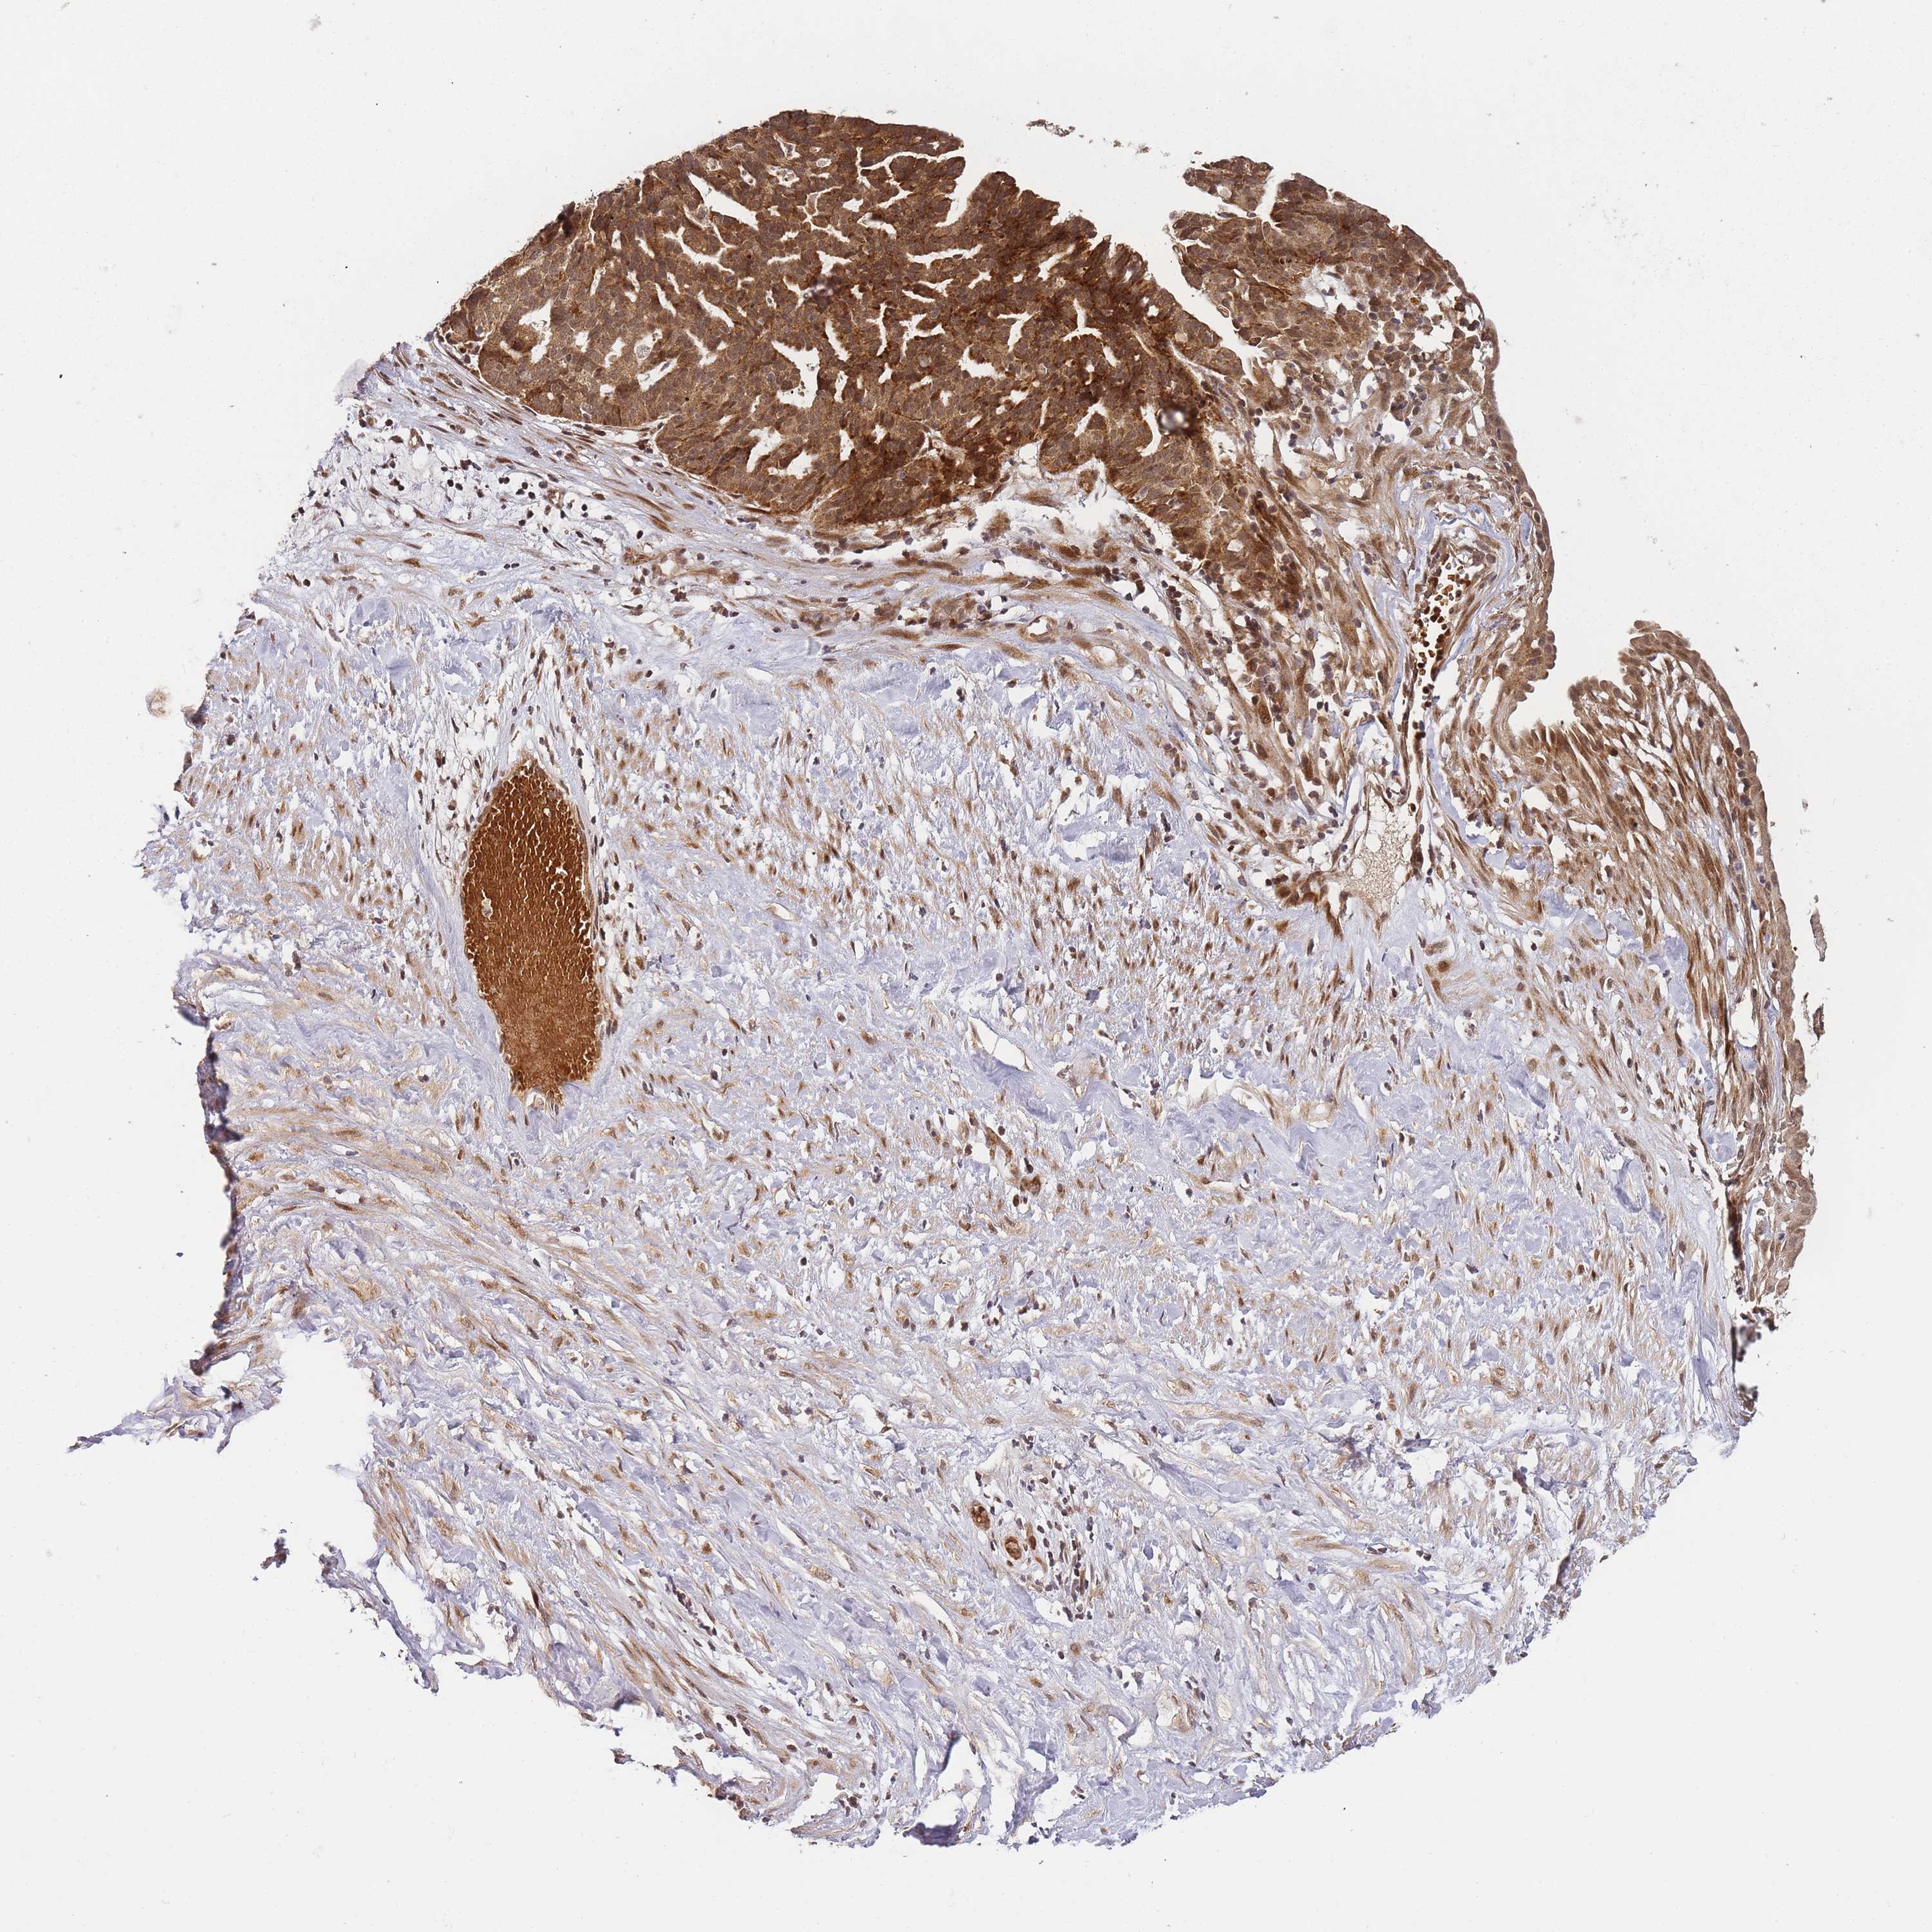

OVARIAN CANCER - Protein expressioni

A mouse-over function shows sample information and annotation data. Click on an image to view it in a full screen mode. Samples can be filtered based on level of antibody staining by selecting one or several of the following categories: high, medium, low and not detected. The assay and annotation is described here.

Note that samples used for immunohistochemistry by the Human Protein Atlas do not correspond to samples in the TCGA dataset.

Antibody stainingi

Antibody staining in the annotated cell types in the current human tissue is reported as not detected, low, medium, or high, based on conventional immunohistochemistry profiling in selected tissues. This score is based on the combination of the staining intensity and fraction of stained cells.

Each image is clickable and will lead to virtual microscopy that enables deeper exploration of all samples and also displays staining intensity scores, fraction scores and subcellular localization as well as patient and tissue information for each sample.

Antibody HPA047872

Staining

High

Medium

Low

Not detected

Intensity

Strong

Moderate

Weak

Negative

Quantity

>75%

75%-25%

<25%

None

Location

Nuclear

Cytoplasmic/membranous

Cytoplasmic/membranous,nuclear

Cystadenocarcinoma, serous, NOS

Carcinoma, NOS

Cystadenocarcinoma, mucinous, NOS

Carcinoma, endometroid